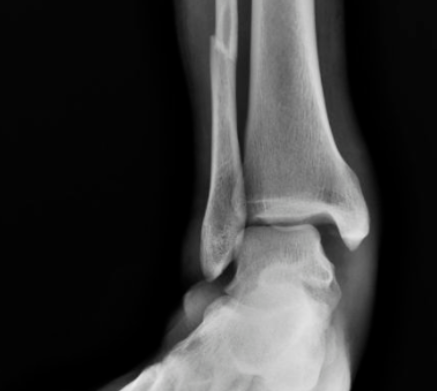

#踝关节骨折

踝关节撞击综合征!

踝关节骨折术后康复动作

后踝骨折及下胫腓联合螺钉取出时机与下胫腓不稳的关系

对合并下胫腓联合损伤的内外踝骨折或三踝骨折,常规置入下胫腓螺钉,同时为避免螺钉断裂,恢复下胫腓微动,术者常规在术后6-8周或术后3月取下胫腓螺钉,但下胫腓螺钉取去存在下胫腓不稳风险。为研究双踝/三踝骨折下胫腓螺钉取出的最佳时机,及未固定的后踝与下胫腓稳定性的关系,有学者进行了相关研究,结果发表在近期Injury期刊上。

如何预测Danis-Weber B型踝关节骨折下胫腓联合损伤?

Lauge-Hansen分型与Danis-Webe分型为最常见的踝关节骨折分型,在对下胫腓韧带损伤的指导意义上,旋后外旋II°骨折通常认为合并下胫腓前韧带的损伤,下胫腓联合趋于稳定,可能无需下胫腓联合螺钉固定。而Danis-Weber B型骨折定义为骨折位于下胫腓联合水平,可能合并下胫腓联合损伤。